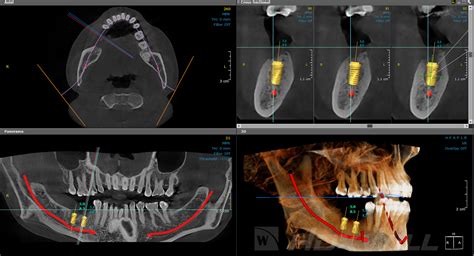

La tomografía computarizada de haz cónico (CBCT, del inglés Cone-Beam Computed Tomography), también conocida como tomografía volumétrica digital de haz cónico, es una técnica de imagen seccional en 3D que ha ganado popularidad en odontología. Esta tridimensionalidad permite visualizar desde diferentes ángulos de vista (nivel superior, inferior, frontal anterior o posterior, vista de sección o lateral).

Las ventajas del Cone beam ya están bien determinadas en todos los campos de la imaginería dentomaxilar. Debido a sus cualidades de doble medición y la precisión que aporta gracias a su particularidad isotrópica que garantiza mediciones lineales exactas, el CBCT se aplica en implantología que necesita mucho uso de la biometría.

Permite establecer una evaluación preoperatoria del diagnóstico tras un examen clínico y radiológico estándar del paciente, para establecer la conveniencia de la colocación del implante en caso de duda o establecer la contraindicación, y en algunos casos para realizar el seguimiento postoperatorio.

La muestra está compuesta por 9 casos con edad media de 16,6± 3,5 años, en un rango de 13 a 24 años, que presentaban una dimensión transversal reducida del maxilar con cierre incompleto de la sutura palatina y que requiriesen tratamiento ortodóncico con ayuda de expansión maxilar para su corrección, siguiendo los criterios de inclusión y exclusión establecidos. A los miembros de la muestra se le tomó un CBCT al inicio y otro al final del tratamiento con MARPE (18 CBCT) con parámetros de exposición de 90 KV, 14 mA, con un tiempo de exposición de 12 segundos, tamaño de vóxel de 0,2 Vox y 8×8 FOV. El tiempo de reconstrucción de la imagen fue de aproximadamente 2 minutos.

El expansor empleado consistió en un tornillo de expansión de 8, 10 o 12 mm de longitud, seleccionado para cada paciente en función de la necesidad de expansión y la profundidad del paladar según recomienda el grupo de Moon. Dicho tornillo se presenta con cuatro orificios de 2 mm de anchura cada uno, los cuales actuarán como guía de inserción de cuatro minitornillos con dimensiones de 1,8 mm de diámetro y entre 9, 11 y 13 mm de longitud (microtornillos BMK modelo ACR de Recursos Médicos), habiendo sido seleccionados previamente su longitud en función de la disponibilidad ósea hasta el suelo del seno y que permitirán la estabilización del disyuntor evaluada en el CBCT.

Como el objetivo era medir la diferencia volumétrica del ápice radicular de premolares y molares tras la disyunción, se segmentaron los dientes utilizando el software Romexis de Planmeca. Se realizó de manera aleatoria por dos observadores de manera independiente, con el fin de ver la calibración interoperadores de este procedimiento. Primero para ello se hizo un protocolo conjunto del procedimiento que describimos a continuación:

- Situar en el espacio el diente a medir. Para ello se situaban los planos de referencia siguiendo el eje axial en cada uno de los dientes, tomando como referencia el límite apical de la cámara pulpar del molar.

- Con la herramienta de segmentación, plano por plano se va dibujando la forma.

- Una vez terminado se exportaba como archivo STL.

Para medir el volumen, esos archivos STL eran volcados en pares que correspondían a las fases de evaluación de T1 y T2 para el mismo diente al software Geomagic. En este momento, el volumen ya podía calcularse para cada diente de manera individual. Como se observa en la foto, se identifica un diente 14 marcado en verde en post-tratamiento y el que está “oculto” corresponde al 14 pre-tratamiento.